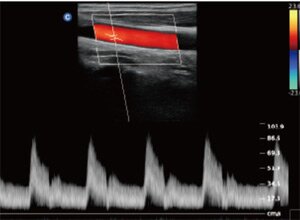

Клинические изображения